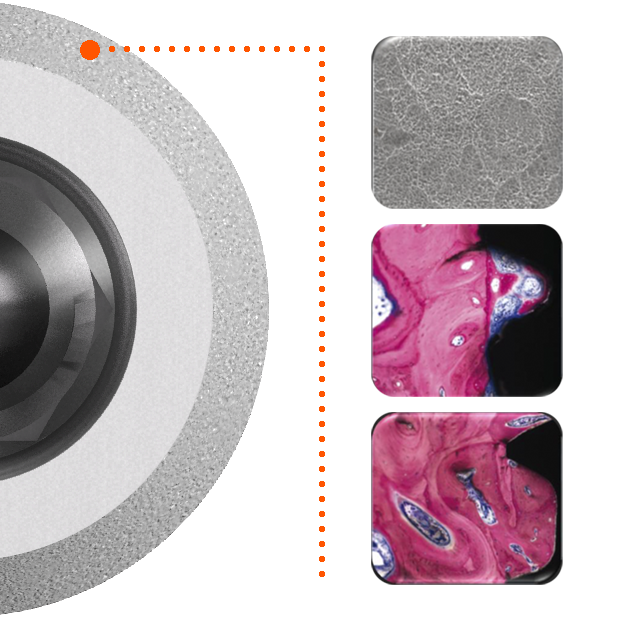

Sur le plan biologique, le positionnement de l’épaulement de l’implant a été revisité de façon à ce que le chanfrein rugueux puisse se situer sous l’os cortical. L’objectif de ce positionnement est de décharger la crête osseuse de toute contrainte et de recréer un environnement favorable au sertissage de l’implant(1).

Car ce sont les tables osseuses péri-implantaires qui soutiennent la muqueuse et contribuent au rendu esthétique des restaurations.